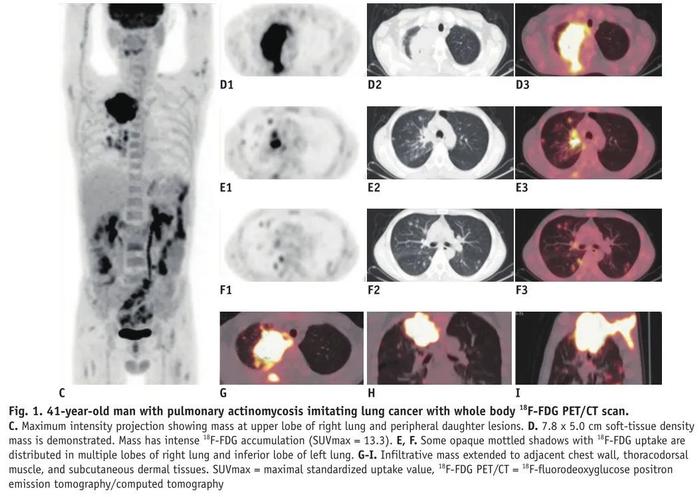

图7 肺部放线菌病影像学表现部分时候,肺部放线菌病的影像学表现和肺癌类似(图8),做PET-CT都难以鉴别。

图8 PET-CT扫描

图8 PET-CT扫描肺部放线菌病的影像学表现有时候侵犯胸壁(图9),与肿瘤、结核鉴别困难。